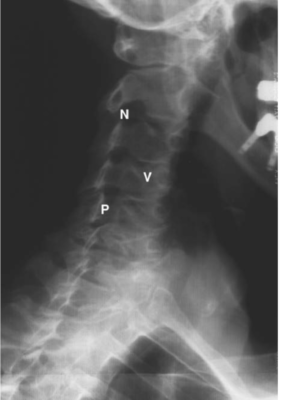

LIÊN HỆ HÌNH ẢNH HỌC

Cột sống cổ

Các chữ viết tắt:

- V = Vertebral body; thân đốt sống

- D = Intervertebral disc; đĩa gian sống

- Sc = Spinal cord; tuỷ sống

- S = Spinous process; mỏm gai

- N = Neural foramen; lỗ thần kinh

- P = Pedicle of vertebral arch; cuống cung

- I = Intervertebral disc space; khoảng đĩa đệm

- F = Facet joints; khớp diện nhỏ/facet

- T = T1 transverse process; mỏm ngang T1

Cột sống thắt lưng